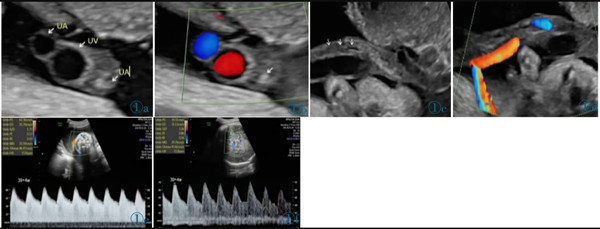

11 例中孕期超聲均可見2 條UA(膀胱水平橫切面顯示2 條UA 血流信號),超聲最后一次提示可見2 條UA 的平均孕周為(31.2±3.1)周。11 例超聲首次提示UA 數(shù)目異常(表現(xiàn)為膀胱水平橫切面UA彩色多普勒僅顯示1 條UA 及血流信號,另一側(cè)血流信號消失)的平均孕周為(36.7±2.8)周,6 例(54.4%)為膀胱左側(cè)血流信號消失,5 例(45.5%)為膀胱右側(cè)血流信號消失。7 例(63.6%)孕晚期超聲首次即提示單條UAT,這7 例臍帶游離段橫切面二維灰階圖像均顯示3 個管腔結(jié)構(gòu),其中1 條UA 內(nèi)可見稍高回聲填充且血流信號消失(圖1);1 例(9.1%)在孕34+4周提示單臍動脈,在孕37 周超聲隨訪中糾正診斷為單條UAT,因超聲提示臍帶高度螺旋,且在臍帶橫切面下見臍靜脈呈“C 形”包繞2條UA,1 條UA 內(nèi)存在血栓回聲(圖2),該病例同時合并胎兒生長受限;3 例(27.3%)整個孕期均提示單臍動脈,回顧其既往中孕期超聲均見2 條UA,晚孕期超聲發(fā)現(xiàn)1 條UA 內(nèi)存在血栓回聲(圖3)。

圖1a 臍帶橫切面。1 條臍靜脈管腔大,內(nèi)為無回聲。2 條UA 管腔小,栓塞側(cè)內(nèi)為稍高回聲(血栓回聲),通暢側(cè)內(nèi)為無回聲。圖1b 臍帶橫切面。臍靜脈及通暢側(cè)UA 內(nèi)見方向相反的血流信號,栓塞UA內(nèi)無血流信號(箭頭所示)。圖1c 臍帶縱切面。臍靜脈內(nèi)為無回聲,栓塞UA 內(nèi)等回聲為血栓(箭頭所示)。圖1d 臍帶縱切面。臍靜脈內(nèi)可見血流信號,栓塞UA 內(nèi)無血流信號。圖1e 通暢側(cè)UA:舒張末期血流流速增加,S/D 和PI 偏低。圖1f MCA:舒張末期血流流速增加,PI 值降低。Figure 1a.Cross section of cord.No echo is shown in the lumen of umbilical vein(the larger one).Two UAs have smaller lumens,and hyperecho is found in the occluded UA(thrombus).Figure 1b.Cross section of cord.Opposite blood flows are shown in umbilical vein and the normal UA,and no blood flow signal is shown in the occluded UA(as indicated by the arrow).Figure 1c.Longitudinal section of cord.There is no echo in umbilical vein and the arrow indicates the thrombus in the occluded UA.Figure 1d.Longitudinal section of cord.There is blood flow in umbilical vein and no blood flow in the occluded UA.Figure 1e.The unobstructed UA: the end diastolic blood flow velocity increases;S/D and PI decreases.Figure 1f.MCA: the end diastolic blood flow velocity increases;PI decreases.

圖2 a 臍帶橫切面。臍靜脈呈“C 形”包繞2 條UA,1 條UA 內(nèi)存在血栓回聲(T:血栓)。圖2b~2d 臍帶高度螺旋。Figure 2 a.Cross section of umbilical cord.One clogged UA is in parallel with the other unobstructed one and both of them are surrounded by umbilical vein(T: thrombi).Figure 2b~2d.Hyper-coiling of umbilical cord.

圖3 誤診為單臍動脈病例的超聲圖像。圖3a:孕24+4 周,膀胱兩側(cè)均可見UA 血流信號;圖3b:孕37+1 周,膀胱一側(cè)UA 血流信號消失;圖3c:臍帶橫切面見臍靜脈呈“C 形”包繞2 條UA,箭頭所示其中1 條UA 管腔細(xì)小,內(nèi)為稍高回聲(血栓)填充。圖4 臍帶病理(HE 染色)。UA 內(nèi)見血栓形成,管壁彈力纖維梗死。Figure 3.Ultrasonography misdiagnosed as single umbilical artery.Figure 3a: At 24+4 weeks,the blood flow of two UAs is seen in both sides of bladder.Figure 3b: At 37+1 weeks,only one UA is seen in the level of bladder.Figure 3c: In the cross section of umbilical cord,two UAs are surrounded by umbilical vein.As indicated by the arrows,one UA has smaller lumen which is filled with a slightly higher echo(thrombi).Figure 4.The pathological finding of umbilical cord (HE stain).The UA lumen is filled with thrombi.The necrosis of elastic fibers are found in arterial wall.